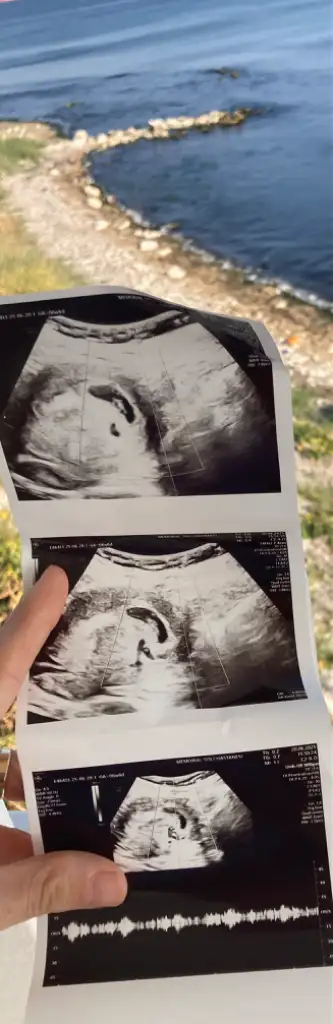

Bana da bakar mısınız lütfen biri 9 haftalık biri 6 haftalık karından ultrasonKese şekline göre erkek bence. Sağlıkla kucağınıza alın

Banada bakar mısnız lütfennnn çok merak ediyorum biri 9 haftalık biri 6 haftalık ultrason karından

Nuba göre ankıyormusunuz acaba?Bariz görünüyor kız diyorum

Sizin de karından ultrason mıBanada tahmin yapar msnzzz

EvetttSizin de karından ultrason mı